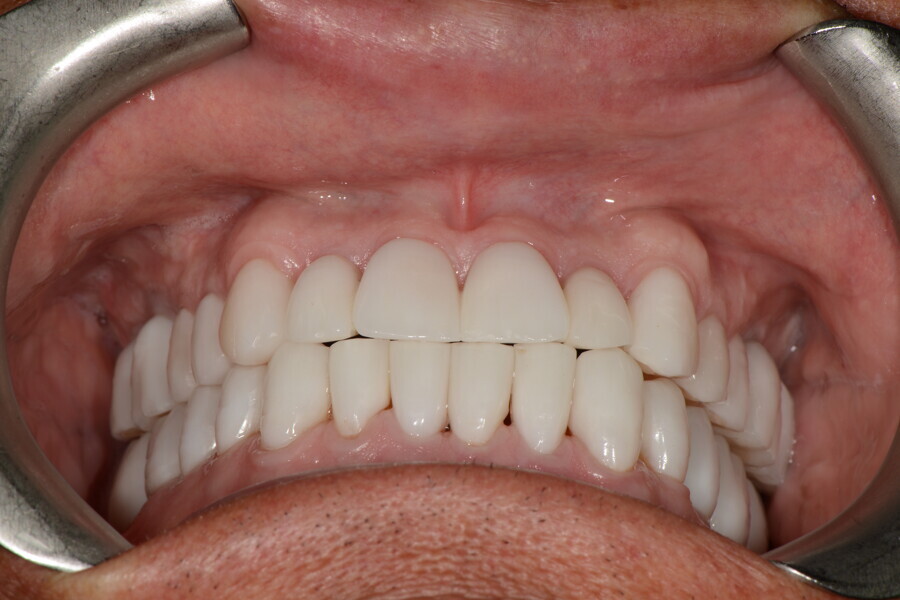

After the first phase of aligner treatment, we had achieved better inter-arch coherence, better maxillary arch expansion, and some space for improving the anterior tooth proportions restoratively (Fig. 19). We then temporarily restored the anterior teeth directly with composite, closing the spaces, improving the tooth proportions and further increasing the maxillary arch expansion (Fig. 20). We used restorative arch expansion to reduce the orthodontic destabilisation of the teeth to achieve the correct inter-arch coherence and retain the teeth in the cortical bone.38 A refinement aligner phase was undertaken to improve the final alignment of the gingival zenith and to improve the inter-arch coherence (Fig. 21). The periods of the first orthodontic phase and of the refinement were used to augment the mandibular and maxillary bone and to place the implants (Fig. 22). At the end of the orthodontic treatment, the case was finalised with ceramic veneers in the anterior area and temporary restorations on the implants in the posterior area (Figs. 23–26).

The provisional phase of about four months was important to allow the peri-implant tissue to mature and to teach the patient to chew correctly with chewing gum, cotton rolls and silicone masticatory sticks. This is fundamental training for the patient to achieve the correct alternating unilateral masticatory cycle needed to obtain the ideal rehabilitation of the masticatory system. We wanted the patient to achieve ideal masticatory and swallowing function. After sufficient rehabilitation time, we finalised the case with posterior zirconia crowns screwed on to the implants (Fig. 27).26

Our ideal final rehabilitation goals were:

• posterior stability;

• inter-arch coherence and U-shaped arches;

• anterior freedom during mastication;

• minimum disclusion vertical dimension;

• alternating unilateral masticatory cycle;

• physiological swallowing and high tongue posture against the palate; and

• mandibular disclusion advancing the mandible freely.